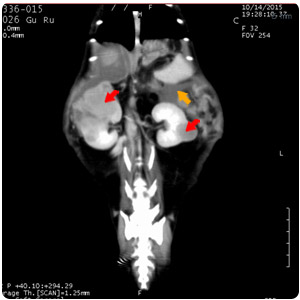

| 腎臟腫塊(紅)、腹水(黃) |

腹水(紫)、腹部腫塊(紅)、腎臟腫塊(黃) |